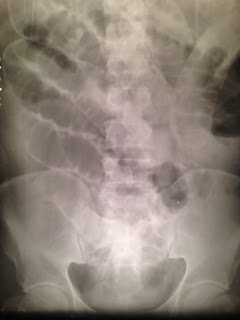

| Streptokinase. Credit: Wikipedia |